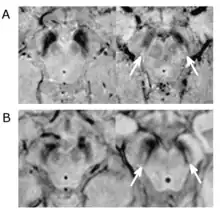

Le diagnostic de maladie de Parkinson est habituellement clinique. En théorie, la certitude du diagnostic n'est obtenue que par l'étude histologique du cerveau mais les critères diagnostiques actuellement définis permettent de faire le diagnostic sans trop de difficultés. Le scanner cérébral par tomodensitométrie des personnes atteintes de la maladie de Parkinson est habituellement normal[123]. L'imagerie par résonance magnétique sensible au fer (IRM T2*) peut être utilisée dans un cadre diagnostique. En effet, le fer peut être témoin de la mort cellulaire et le signal T2* diminue en présence de fer tandis que son inverse (R2*) augmente[124]. Dans la maladie de Parkinson, il existe une concentration en fer trop importante par rapport à la moyenne pour le même groupe d'âge au sein de la substance noire du fait de la perte de neurones dopaminergiques[125]. De plus, l'imagerie pondérée en fonction de la susceptibilité est elle aussi un marqueur fiable de la présence de fer intracérébral en étant à la fois sensible et spécifique à la maladie[126]. L'IRM T2* et l'imagerie pondérée en fonction de la susceptibilité sont toutes deux capables d'afficher le signe d'effacement de la queue d'hirondelle (swallow tail) dans la substance noire dorsolatérale. La tomodensitométrie et l'IRM sont également utilisées, en pratique clinique, pour écarter d'autres maladies pouvant engendrer un syndrome parkinsonien telles que l'encéphalite, les AVC chroniques, les tumeurs des ganglions de la base et l'hydrocéphalie[123].